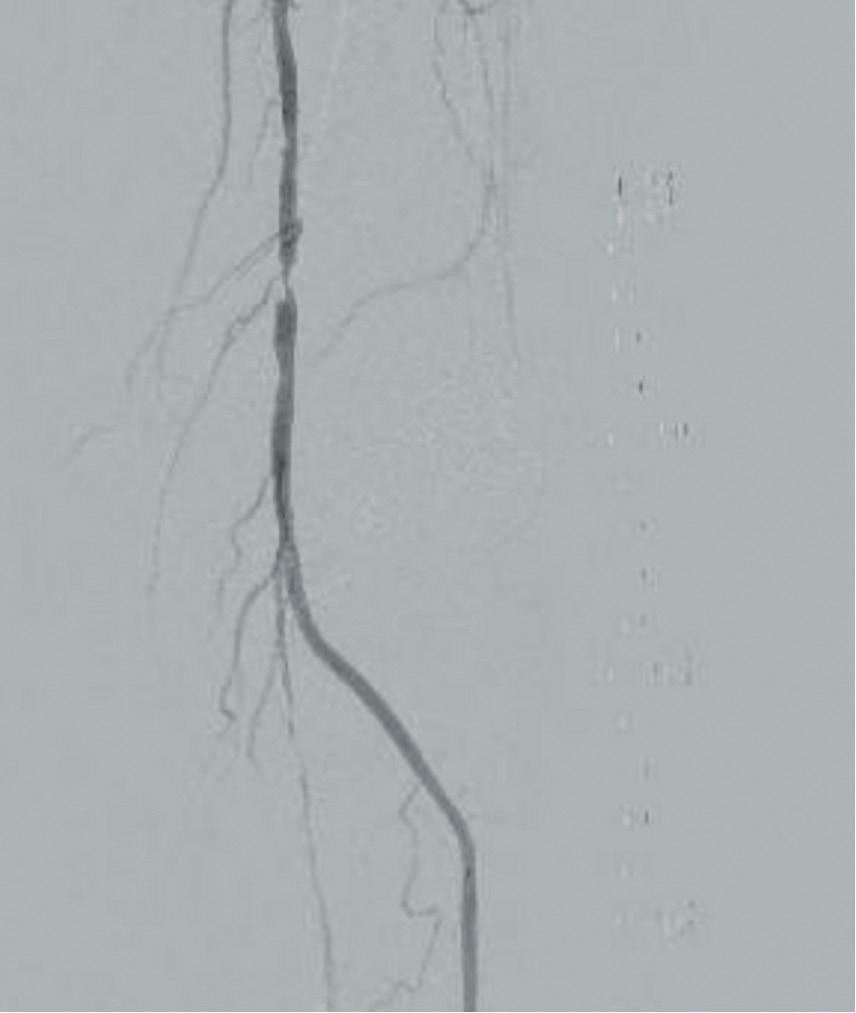

He was taken to the cath lab and underwent a right lower-extremity arteriogram. This confirmed a 90% stenosis of the distal SFA, with normal three-vessel run off. Due to the heavy calcium, we opted for a Shockwave M5+ 6x60mm and delivered 200 pulses to the lesion. There was no appreciable residual stenosis at the completion of the procedure, and his post-procedure ABI improved to 1.

This is a great example of how IVL can be used as a standalone therapy without the need for adjunctive treatment.

Figure 5. Final angiogram

Figure 3. Post-IVL angiogram

Figure 3. Final angiogram